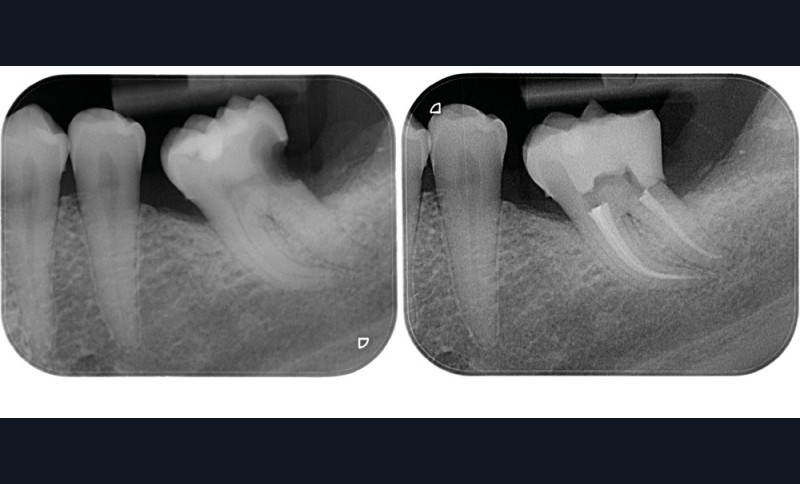

Une cavité d’accès trop petite [2] optimiserait le pronostic biomécanique (préservation dentaire maximale) mais pourrait compromettre le pronostic endodontique : mauvaise lecture de l’anatomie, instrumentation partielle, non ergonomique et avec risque de fracture, défaut de nettoyage des parois canalaires [3], irrigation inadéquate, difficulté d’obturation canalaire, voire d’obturation coronaire. Ce sera le cas des cavités d’accès « Ninja » [4] ou ultraconservatrice (fig. 1), des cavités d’accès « Truss » [5] (fig. 2), des cavités d’accès dites « opportunistes » [6] (fig. 3).

Une cavité d’accès trop large optimiserait le pronostic endodontique mais compromettrait le pronostic biomécanique. C’est le cas de la cavité d’accès traditionnelle, qui a longtemps été « au service » du praticien réalisant le traitement canalaire (dentist-centered dentistry ou dentisterie centrée sur le praticien). Les étapes d’instrumentation, d’irrigation et d’obturation étaient ainsi facilitées grâce à des accès visuel et instrumental exagérés, aux dépens de structures dentaires saines (fig. 4).